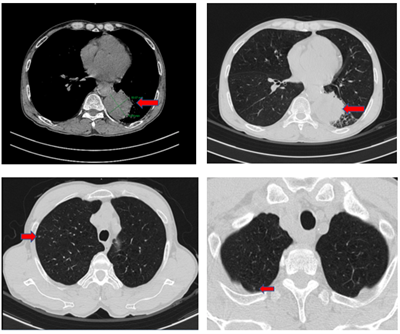

Ca lâm sàng:Hiệu quả điều trị đích bằng Osimertinib ở bệnh nhân UT biểu mô tuyến của phổi giai đoạn IV có đột biến gen EGFR L858R (Exon 21) tại Trung tâm YHHN&UB-Bệnh viện Bạch Mai

Ca lâm sàng:Hiệu quả điều trị đích bằng Osimertinib ở bệnh nhân UT biểu mô tuyến của phổi giai đoạn IV có đột biến gen EGFR L858R (Exon 21) tại Trung...

Ngày đăng: 29/01/2026

Ung thư phổi là một trong những ung thư có tỷ lệ mắc và tử vong cao nhất trên toàn thế giới. Theo GLOBOCAN 2022, ung thư phổi đứng thứ hai về số ca mắc mới với khoảng 2,5 triệu trường hợp mỗi năm và...